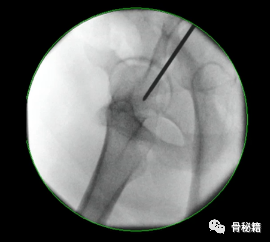

1、进钉点。髓内钉的位置在哪里最合适?

当然是髓腔的最中心,所以髓腔最中心的延长线就是最佳的进钉点。一般位于梨状窝。一个好的进针点可以保证力线,同时进钉后还有复位的作用,如果进钉点出现了偏移,可能整个手术都会有影响。好的开始象征着接下来手术的顺利,一定要取一个好的进针点。

他在正侧位的透视位置我们可以看到位于髓腔中心的延长线上

随着有外翻角的髓内钉的发明,我们现在目前用的可能多是大粗隆顶点进针的了

进针的角度,基本与股骨颈是垂直的角度

我们在做粗隆间骨折的时候由于骨折线经常经过进针点而出现近端内移的情况

注意采用快钻慢进,用套筒来纠正方向。